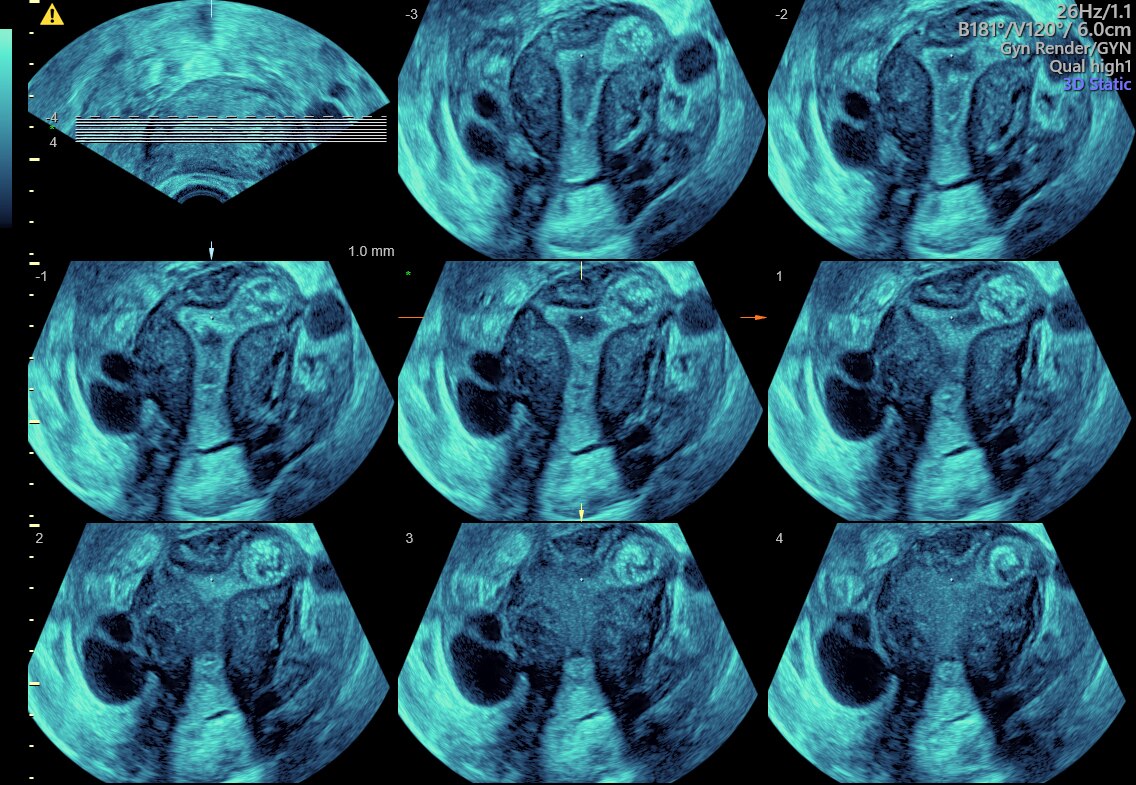

Tomographic ultrasound imaging (TUI) of uterine cavity